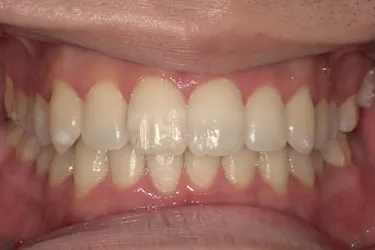

人と接する機会が多く、第一印象を大切にしたいと考え、写真写りや笑顔への自信を高めたいという思いから矯正を決意された矯正当時学生だった22歳男性の H.S.様に、スマイルモア矯正を選んだ理由を伺いました。

| 詳細情報 | |

|---|---|

| 費用 | 360,000円(税込396,000円) |

| 治療期間 | 11ヶ月 |

| 治療内容 | マウスピースを用いた歯列矯正 |

| 追加処置 | IPR |

以前よりも歯並びが改善され、人とコミュニケーションをとることに自信がつきました。 「スマイルモア」という名前の通り、笑顔に自信がついたことで今までよりも口を開けて笑う機会も増えました。 矯正期間が年単位だったのですぐに変化があったわけではないですが、綺麗な仕上がりに満足しています。